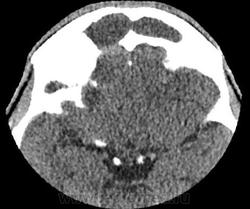

К делу подключились нейрохирурги, больной был экстренно прооперирован. Произведена КПТЧ, удаление субдуральной эмпиемы лобно-височно-теменной области справа, постановки дренажа под ТМО. Также вскрыты передние стенки обоих гайморовых пазух, произведена ревизия лобной пазухи, в пазухи заведены тампоны. По образному выражению нейрохирурга, при вскрытии ТМО получили: "Фонтан гноя". Снимки после операции:

Динамика отчетливо положительная, субдуральное гнойное содержимое практически полностью эвакуировано. Дислокация срединных структур уменьшилась. Определяется постоперационная пневмоцефалия.

Пациент провел 6 суток в реанимации. Состояние стабилизировалось. На 9е сутки пребывания очередное контрольное КТ:

В конвекситальных отделах правой теменной доли появилось несколько гиподенсных локальных зон, плотностью +15+20HU, с четкими неровными контурами; аналогичные зоны в полюсе правой лобной доли +19+25HU и в полюсе правой височной доли - формирующиеся кистозно-атрофические изменения? Сохраняется смещение срединных структур влево на 4мм. В зоне операции (КПТЧ) установлен дренаж, определяются немногочисленные пузырьки воздуха и пластинчатое субдуральное скопление патологического содержимого.

Переведен на ЛОР-отделение. Произведена левосторнняя этмоидотомия. Контрольное КТ головного мозга на 25е сутки пребывания.

Умеренная положительная динамика. Сохраняется зона формирующихся кистозно-атрофических изменений в лобной и височной долях справа плотностью +2+22HU. Срединные структуры смещены влево на 2 мм.